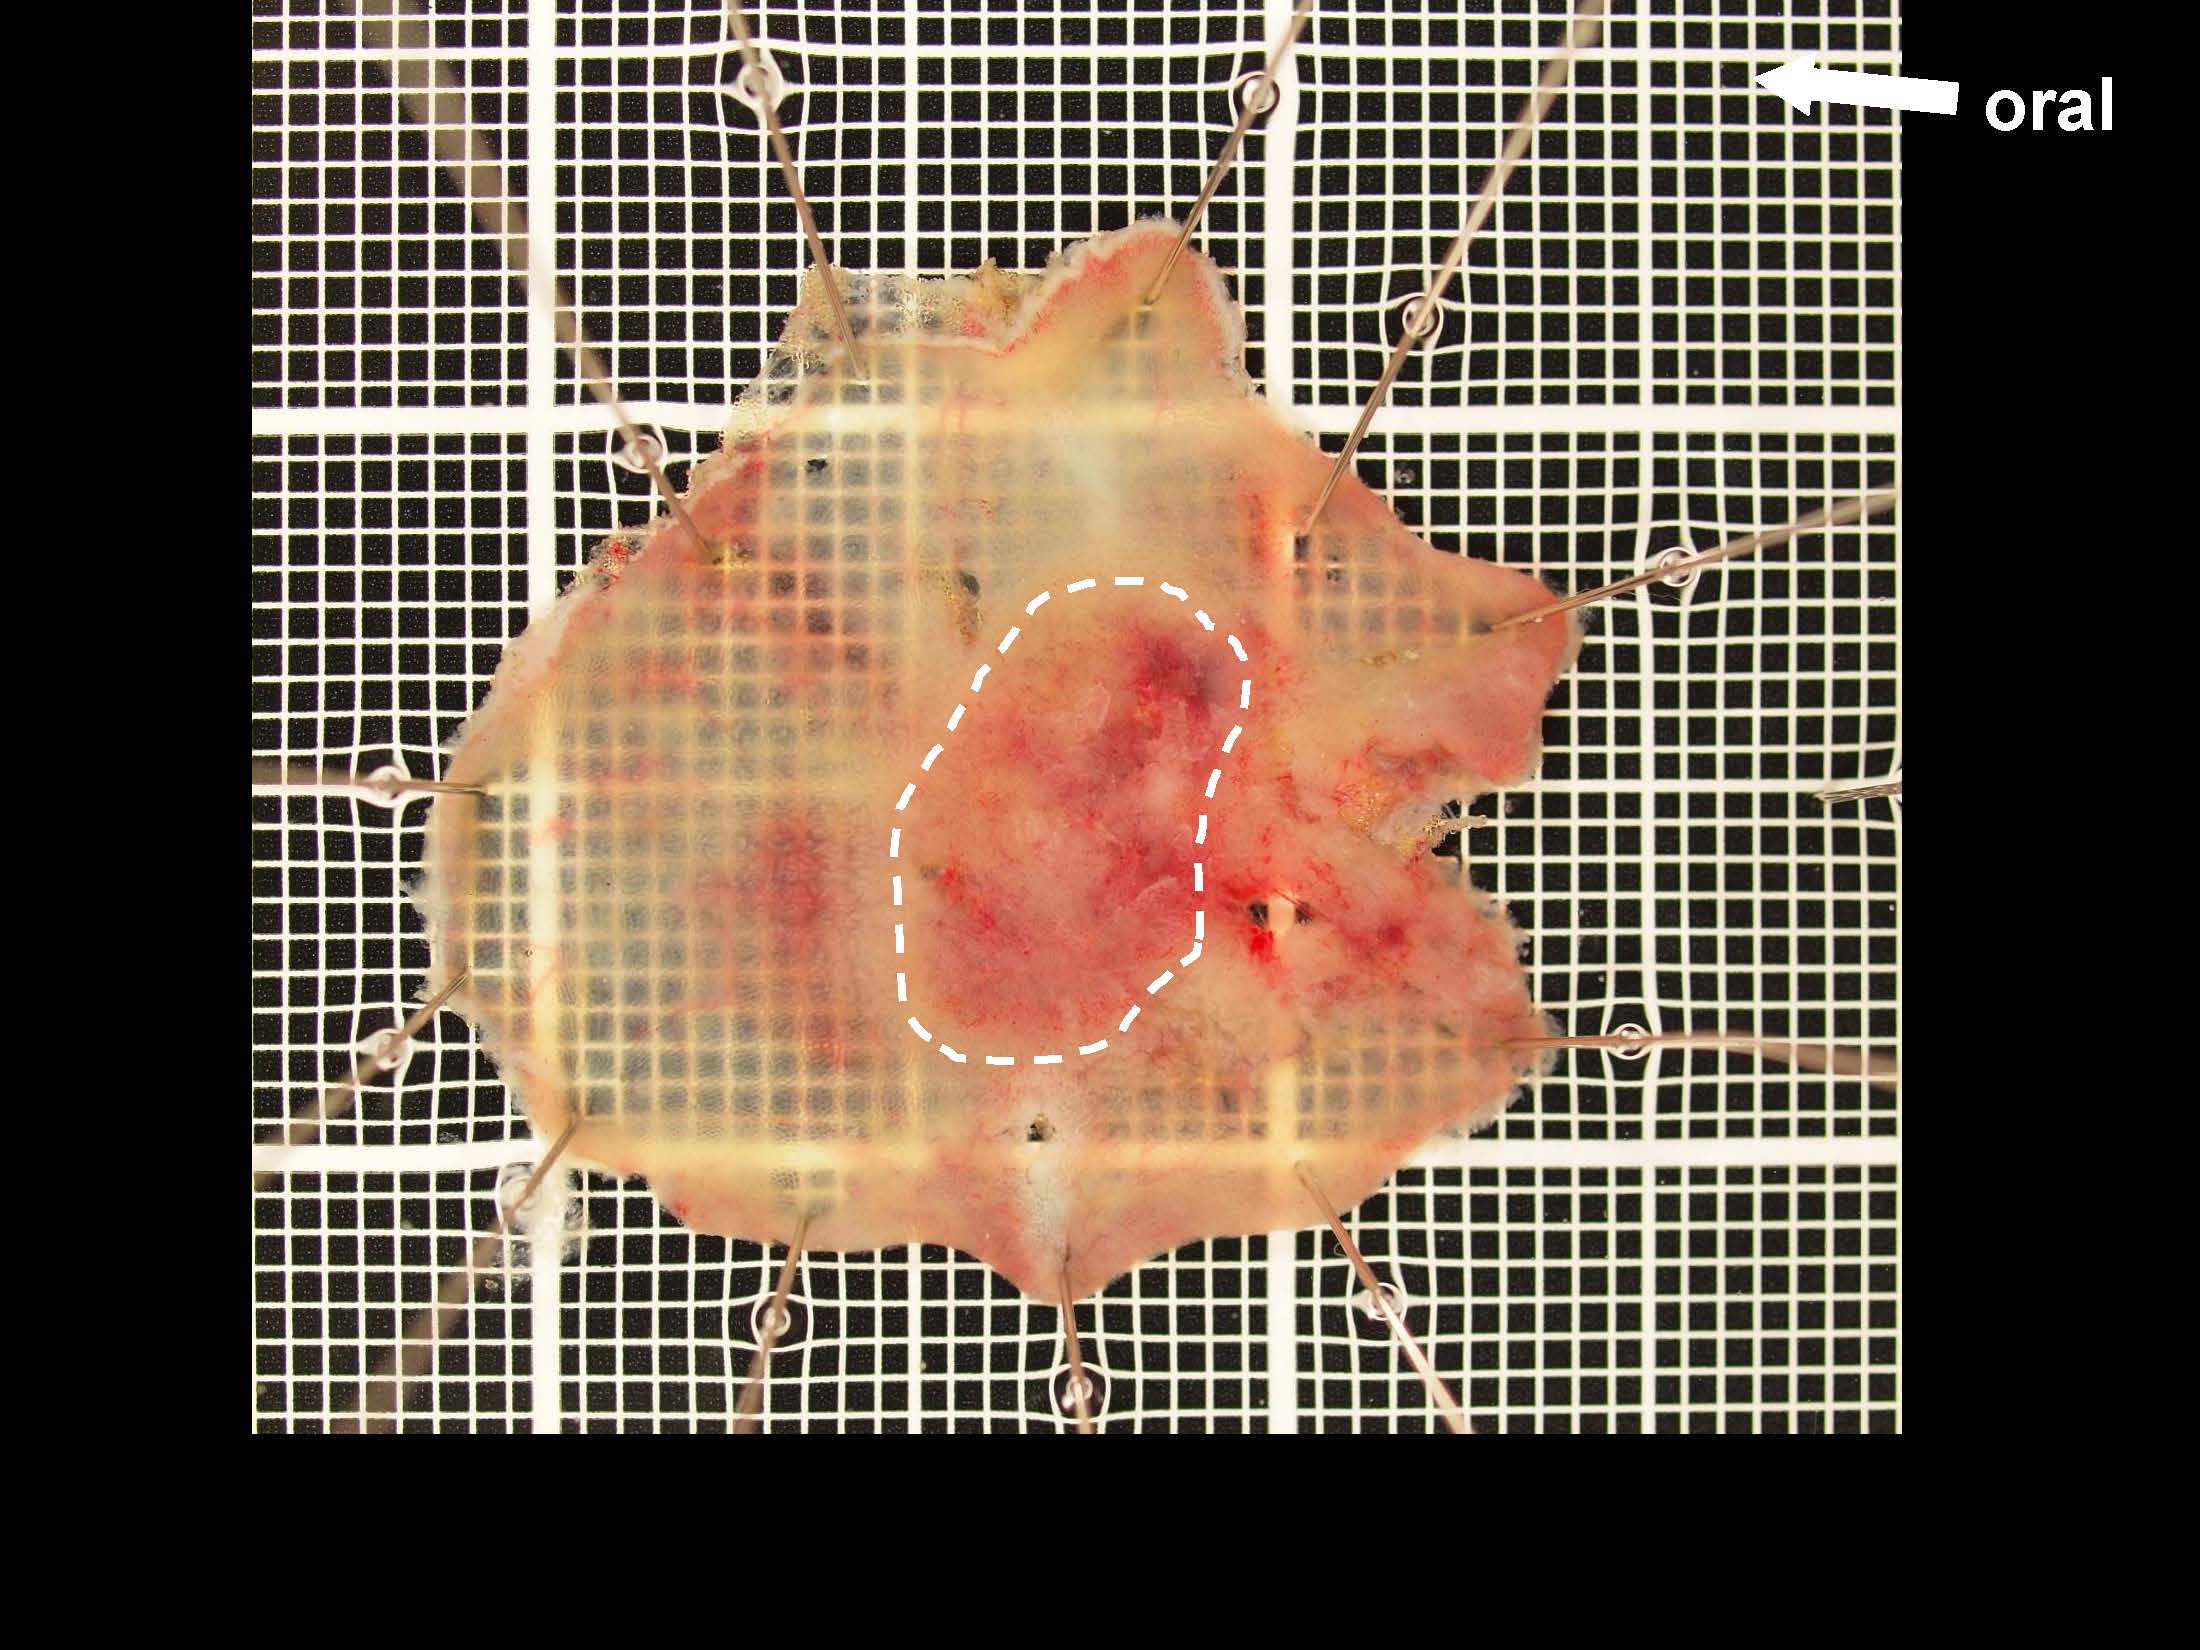

消化管Mapping~大腸~ 2021.10.27

消化管Mapping~大腸~

消化管Mapping